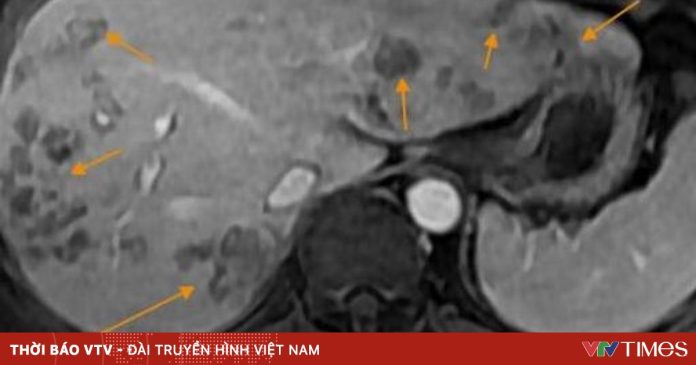

Chụp cộng hưởng từ (MRI) ổ bụng phát hiện nhiều ổ tổn thương khu trú gan phải, nghi do ký sinh trùng. Xét nghiệm chuyên sâu xác nhận bệnh nhân dương tính với sán lá gan lớn và giun lươn. Anh N. được chẩn đoán tổn thương gan do sán lá gan lớn kèm rối loạn lipid máu, bác sĩ kê phác đồ điều trị và hẹn tái khám sau 1 tháng.